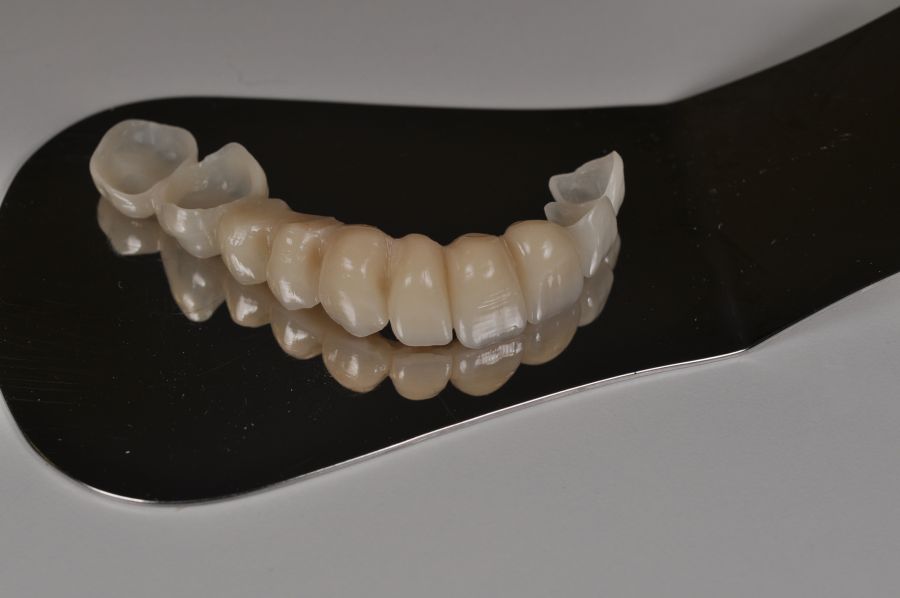

Para la fabricación de las estructuras, se eligió el óxido de zirconio monolítico como material restaurador sobre interfases metálicas en el puente implantosoportado, y coronas de óxido de zirconio monolítico en los dientes tallados previamente (1.7, 1.6, 2.2 y 2.3). Se tomaron impresiones de cubeta abierta con silicona de adición pesada y fluida (Zhermack Elite HD, Gmbh). Se realizó una prueba de pasividad analógica y el resto del proceso se confeccionó de manera digital, por lo que se hicieron pruebas estéticas de dientes impresas en 3D sobre interfases metálicas, para hacer todos los ajustes de función y estética previos al fresado del zirconio monolítico (Figuras 11, 12 y 13).

El día de la colocación de las estructuras, se arenó el interior de las coronas dentosoportadas con óxido de aluminio de 50 m y fueron cementadas con cemento de resina Multilink Ò. El puente implantosoportado se atornilló al torque indicado (20Nw) (Figuras 14, 15, 16 y 17).

Las impresiones analógicas y el posterior flujo digital permitieron una correcta planificación protésica. Las estructuras definitivas, confeccionadas en óxido de zirconio monolítico sobre interfases metálicas de titanio, mostraron una adecuada adaptación pasiva tanto clínica como radiográficamente. La prueba estética permitió ajustes oclusales y funcionales mínimos, optimizando el resultado final.